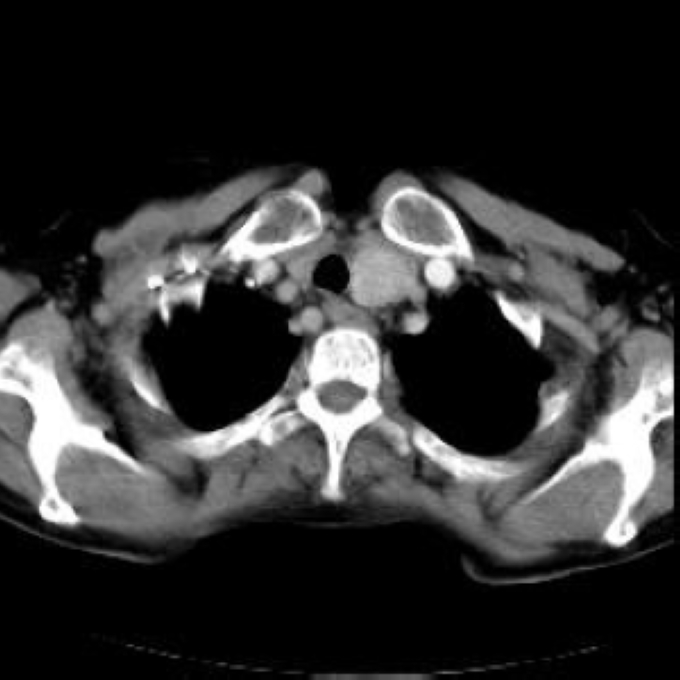

Arteria lusoria.

56 year old patient with dyspagia. A tumor of soft tissue was described in upper mediastinum on plain X-ray of the thorax. What is this mass in the upper mediastinum?